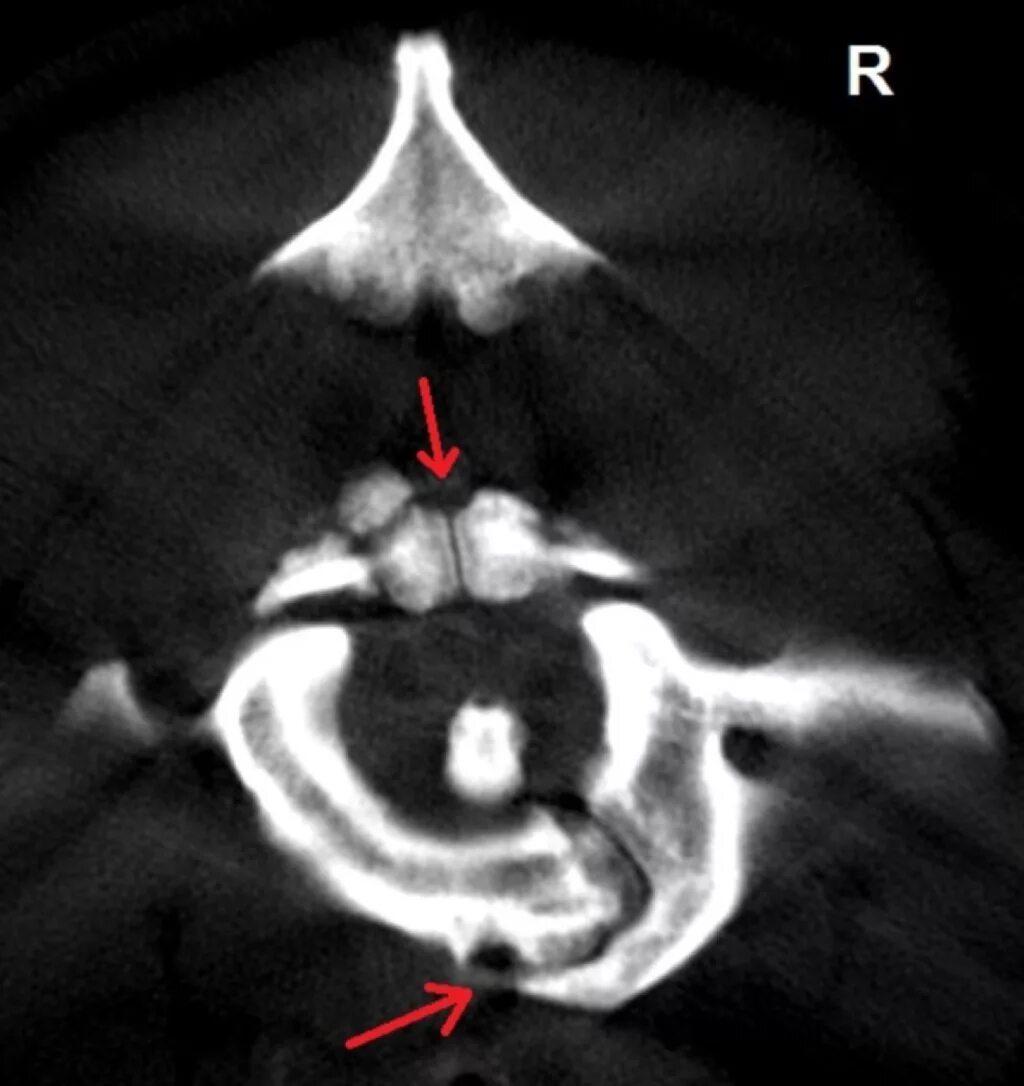

Атлант кт